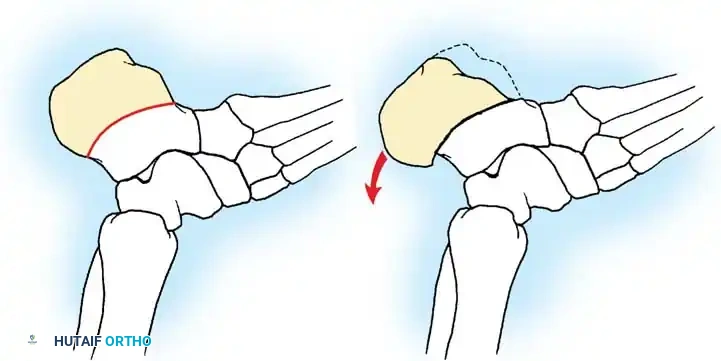

تشوهات القدم في الشلل الدماغي هي حالة شائعة ناتجة عن التشنج العضلي المستمر، وأبرزها القدم الخيلية أو المشي على أطراف الأصابع. يبدأ العلاج بالطرق التحفظية مثل الجبائر وحقن البوتكس، وقد يتطلب تدخلاً جراحياً دقيقاً لتطويل الأوتار وتصحيح العظام لضمان قدرة الطفل على المشي بشكل طبيعي ومستقل.

الخلاصة الطبية السريعة: تشوهات القدم في الشلل الدماغي هي حالة شائعة ناتجة عن التشنج العضلي المستمر، وأبرزها القدم الخيلية أو المشي على أطراف الأصابع. يبدأ العلاج بالطرق التحفظية مثل الجبائر وحقن البوتكس، وقد يتطلب تدخلاً جراحياً دقيقاً لتطويل الأوتار وتصحيح العظام لضمان قدرة الطفل على المشي بشكل طبيعي ومستقل.